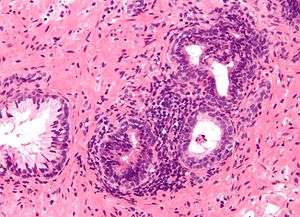

Histology

- Glandular cells

- Myoepithelial cells

- Subepithelial interstitial cells[17]

Prostate Microscopic glands of the prostate

Microscopic glands of the prostate Male Anatomy